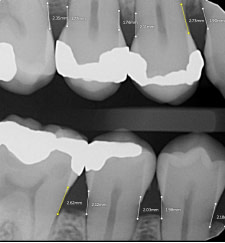

“ToothParts” in Presentations

The ability to toggle the ToothParts feature during case presentations is one of the most powerful patient education tools I have seen.

Visually distinguishing different tooth structures helps patients better understand their conditions and proposed treatments.

In combination with caries and bone loss AI diagnosis, it really works incredibly well and what I appreciate the most about Pearl is that it seems to be designed with presenting to the patient in mind. As its so simple for someone who is non-dental to understand and follow along.

Compare Mode

This feature allows side-by-side viewing of current and historical images. It is useful for demonstrating disease progression or treatment outcomes to patients. Each image in compare mode has its own toolbar, allowing for individual manipulation.

These printouts are particular useful to print out after an examination for patients to take home, helping to improve their understanding and acceptance of the treatment plan. For insurance purposes, the ability to highlight specific findings might help justify treatment recommendations.